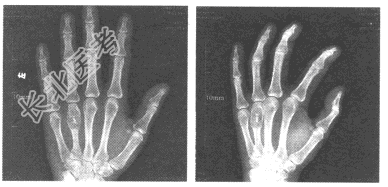

- 单项选择题女,20岁, 左手第4掌骨处局部稍肿痛,质硬, 皮温不高。结合左手正斜位片,最可能的诊断为

A、内生软骨瘤

B、骨结核(骨气臌)

C、骨囊肿

D、骨巨细胞瘤

E、非骨化性纤维瘤